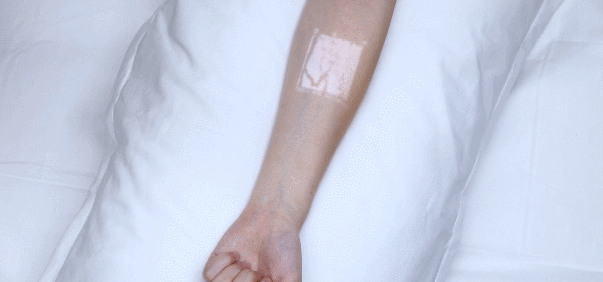

投影式红外血管成像仪

“一针见血”神器

不知大家在医院有没有遇到过

挂水时由于护士找不到血管

被白白扎好几针的经历

那过程想想都瑟瑟发抖

在疫情期间,我国的医疗团队

为提高静脉穿刺效率

便采用了西安中科微光影像技术有限公司

自主研发的投影式血管成像仪

当你把这款仪器照着

需要寻找血管的皮肤区域

它便能直接显示出血管的分布图像

这样医护人员就能

快速地找到血管进行静脉穿刺

以后再也不用白白挨针了

同时它还适用于婴幼儿、老人、

肾病及血管外科等各种临床使用场景

更高级的这仪器的2.0版本

在亮度上还有多种模式可以选择切换

(比如绿光模式、蓝光模式、优化模式

红光模式、紫光模式、深度识别模式等等)

而且还可以拍照

把照片保存在内存卡中

更好的辅助临床进行血管评估

不仅功能强大

外观也很轻巧便捷,可随身携带

该仪器还获得了我国

2019“好设计”金奖